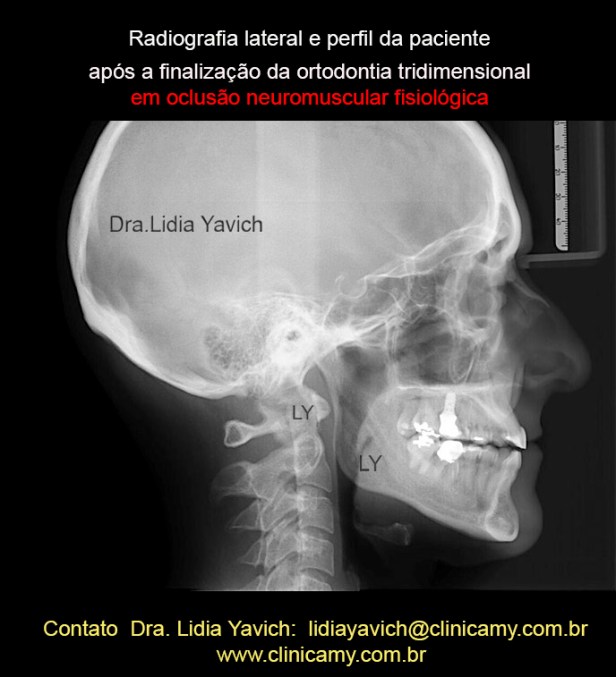

Radiografia lateral e perfil da paciente após a finalização da segunda fase do tratamento mediante uma ortodontia tridimensional e reabilitação neuromuscular fisiológica.

Radiografia lateral e perfil da paciente após a finalização da segunda fase do tratamento mediante uma ortodontia tridimensional e reabilitação neuromuscular fisiológica.